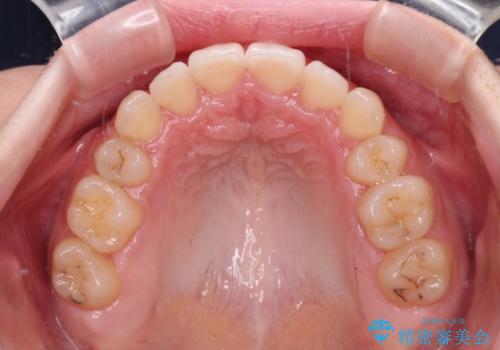

治療期間の目安は2年半~3年間でしたが、予定通り治療が進み、2年半弱で終えることができました。

歯列はきれいに整い、治療期間も予定通りであり、患者様には大変満足していただきました。